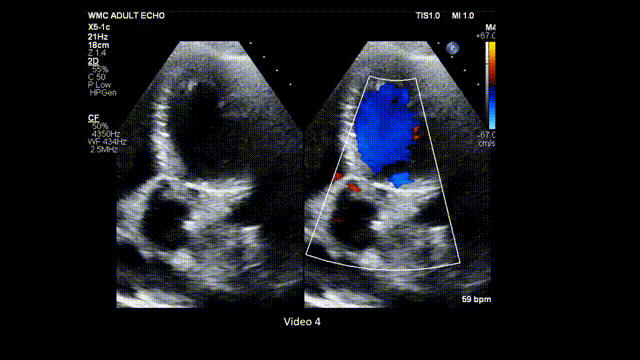

10、心尖三腔心切面: 在主动脉瓣位置使用彩色多普勒评估狭窄所致彩色镶嵌血流模式,并评估主动脉瓣反流(AR)(图11,视频6)。与五腔心切面类似,也需排除其他引起LVOT梗阻的原因。

图11. 心尖三腔心切面评价主动脉瓣狭窄(普通二维和彩色多普勒对比)

心尖三腔心切面:在主动脉瓣处使用彩色多普勒,评估主动脉瓣反流和流出道梗阻所致的狭窄性彩色镶嵌血流模式(stenotic mosaic color flow pattern)。缩写同图2。

视频6. 心尖三腔心切面应用彩色多普勒(彩色与二维灰阶对比模式),观察主动脉瓣有无梗阻性彩色镶嵌血流模式,并评估主动脉瓣反流情况。